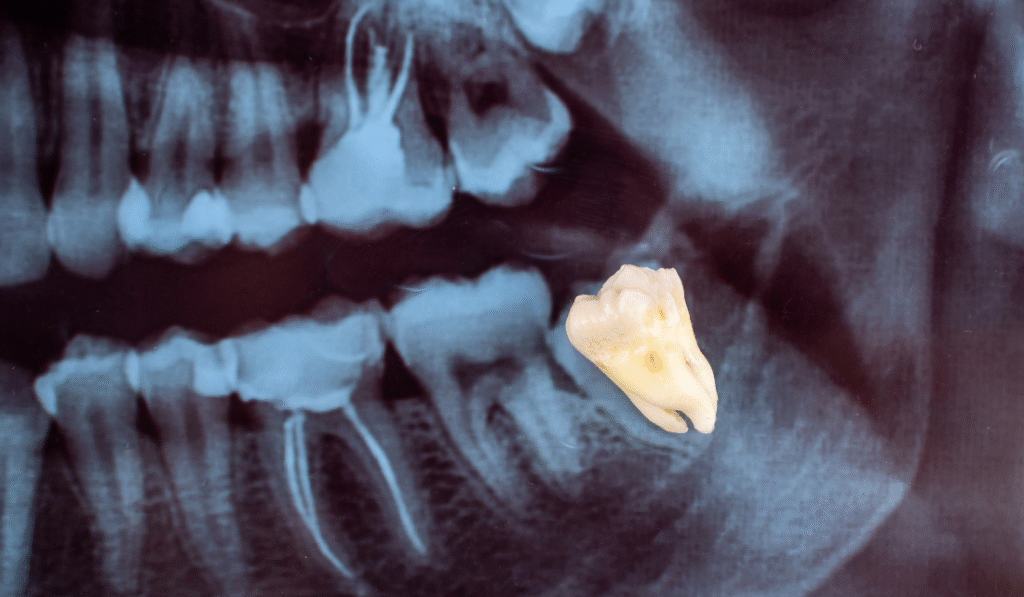

El crecimiento de las muelas del juicio puede acarrear diversos inconvenientes y dolores, afectando a muchas personas durante sus años de juventud y adultez. Uno de los factores más frecuentes que contribuyen a esta molestia es la falta de espacio en la mandíbula. En numerosas ocasiones, la boca no cuenta con la capacidad adecuada para acomodar los terceros molares, lo que genera complicaciones como el impacto dental. Este problema ocurre cuando la muela queda atrapada dentro de las encías, provocando un intenso dolor y presión en la zona afectada.

• El crecimiento de las muelas en ángulos inadecuados puede resultar doloroso. Cuando estas muelas ejercen presión sobre los dientes adyacentes, pueden causar molestias significativas y la necesidad de realizar tratamientos ortodónticos o incluso la extracción del diente afectado.

• Evaluaciones dentales exhaustivas: Realizamos un diagnóstico completo mediante radiografías y exploraciones clínicas para determinar la causa del dolor y evaluar la posición de las muelas del juicio.